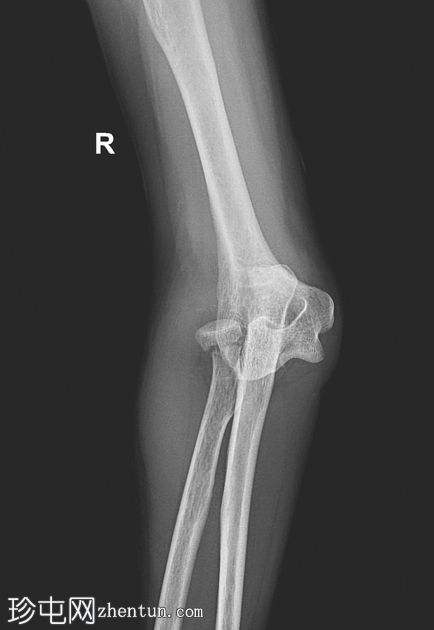

前后位

桡骨和尺骨相对于肱骨远端后脱位

桡骨颈横行骨折,桡骨头骨折块轻度移位

肱骨远端或冠突未见明显骨折

周围软组织肿胀和关节积液